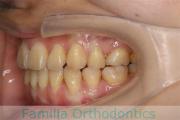

No.23V-478

- 主な症状:

- 叢生

- 年齢:

- 30歳

- 性別:

- 男性

- 抜歯部位

- 上:

- 44済

- 下:

- 8558済

- 主な使用装置:

- FEA 022

- 治療にかかった費用:

- 76万円

右上の歯が重なっているところが邪魔になるとのことで矯正治療を始められた患者さんで、札幌から転院されました。当院で約1年半、15回程度の通院が必要でした。叢生(でこぼこ、凹凸、ガタガタ)が強く、後戻りのリスクが高いケースです。